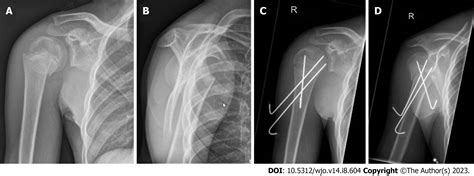

Diagnosis and Treatment

Once you seek medical attention, the doctor will perform a physical examination and order imaging tests such as X-rays, CT scans, or MRIs to determine the extent of the fracture. Based on the diagnosis, the treatment plan will be outlined. Common treatments for a broken shoulder include:

• Surgery: In severe cases, surgery may be required to realign the bones and stabilize the shoulder joint.